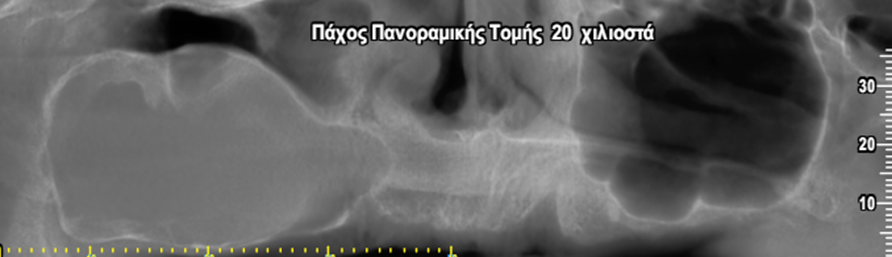

Περίπτωση ιδιαίτερα εκτεταμένης υπολειμματικής κύστης που καταλαμβάνει σχεδόν όλο το δεξιό ημιμόριο της άνω γνάθου εμπλέκοντας και το δεξιό ιγμόρειο άντρο σε γυναίκα ασθενή ηλικίας 75 ετών.

Η κύστη καταλαμβάνει πλήρως τη φατνιακή ακρολοφία στην οπίσθια δεξιά περιοχή της γνάθου και έχει προκαλέσει ιδιαίτερα εκτεταμένη υπέγερση του εδάφους του ιγμορείου άντρου προβάλλοντας εντός αυτού και καταλαμβάνοντας μεγάλο τμήμα της αεροφόρου του κοιλότητας.

Παρατηρείται επίσης ιδιαίτερα εκτεταμένη έκπτυξη και λέπτυνση του πλαγίου τοιχώματος του ιγμορείου άντρου, καθώς και των συμπαγών πετάλων της φατνιακής ακρολοφίας.

Οι δισδιάστατες απεικονίσεις, όπως η πανοραμική ακτινογραφία, συνήθως αδυνατούν να απαντήσουν στο εάν η βλάβη προέρχεται από το ιγμόρειο άντρο ή από τα δόντια της άνω γνάθου.